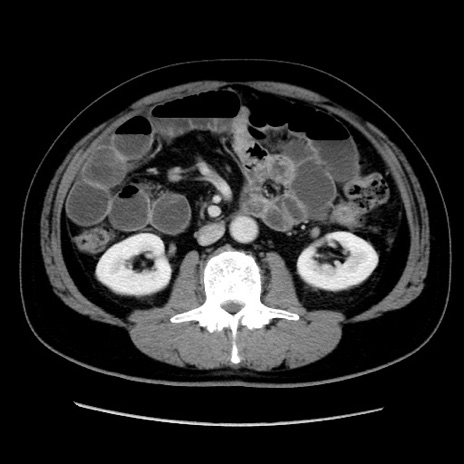

症例16(横断像)

【現病歴】 約1ヶ月前より間欠的に腹痛と嘔吐あり、当院消化器内科を受診したところCTで多発する肝臓のLDAを指摘され、精査中であった。以降は消化器症状は安定していたが、2日前より嘔気と腹痛があり、同日より排便・排ガスが消失した。改善認めず、 本日、救急外来を受診した。